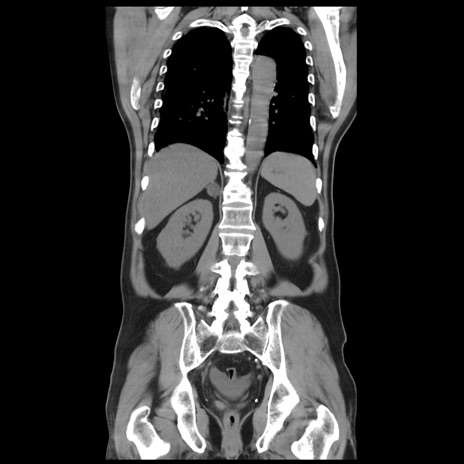

症例20(冠状断像)

【症例】 60歳代男性

【主訴】 腹部膨満、嘔吐

【現病歴】5日前頃より倦怠感を認め食事量減少し4日前の朝嘔吐、食事摂取困難となった。 3日前近医受診し点滴施行され整腸剤などを処方された。 当日他院を受診し、腹部膨満著明、炎症反応の上昇(CRP10.8、WBC11200)あり、紹介受診となる。

【身体所見】 意識JCS1 受け答えがはっきりしないBP 111/57mHg、 P 67bpm、、BT35.2°C、SpO2 97%(RA)、 腹部:膨隆、打診で鼓音あり、全体的に圧痛有り、腸蠕動音(-)、反跳痛ははっきりせず。

【データ】WBC 11400、CRP 14.20